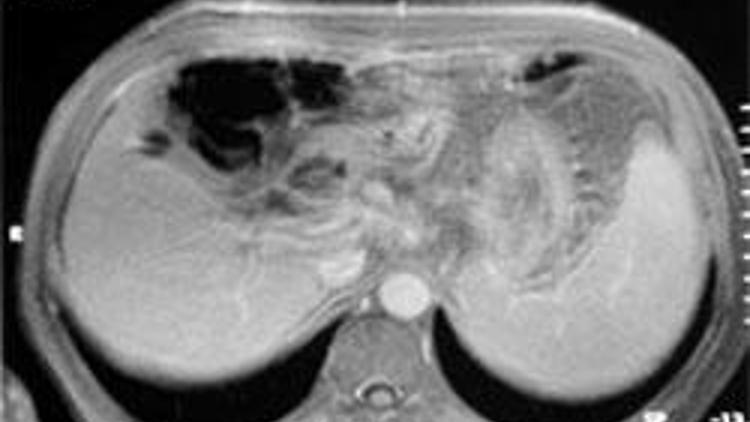

Tomografi ve MR’larda kaliteli görüntü alınmadığında küçük tümörlerin gözden kaçabildiğini belirten doktorlar, “Bilgisayarlı tomografide ince aralıklarla yapılması gereken taramalar birkaç santimetre kalınlıklarında tek fazda, MR incelemeleri ise daha az sekansla yapılıyor. Sonuçta, tümörler gözden kaçıyor, teşhis ve tedavi gecikince de ölümcül sonuçlar doğuruyor” iddiasını dile getiriyor.

KALİTE DÜŞÜYOR, TÜMÖR GÖRÜLMÜYOR

· Küçük bir menisküs yırtığı görünmeyebilir, o ölümcül olmaz ama batın incelemesinde, akciğer incelemesinde yeni gelişmiş bir kanseri ya da onun sıçrama yaptığı başka alanlar görülmeyebilir. Bu da hastanın tedavisinin gecikmesi ya da yanlış tedavi uygulanması gibi sonuçlar doğurabilir. Burada insan hayatı sözkonusu.

· Biz diyoruz ki erken tarama yapalım, erken yakalayalım ama geldiğimiz noktada öyle hizmet veriliyor ki bu mümkün olmuyor. Örneğin meme tümörlerinde biz santim değil milimetre ile uğraşıyoruz. Tümör 2-3 santime ulaştıktan sonra bulmaya başlıyoruz, halbuki amaç onu ele gelmeden milimetrik boyutta yakalamak. Bu, düzgün tarama yaparak olur.